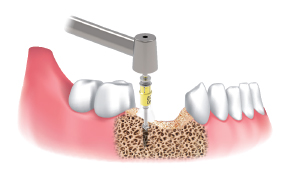

采集顺序 :

使用Ø3.5 / 4.0 / 4.5 / 5.0 / 6.0 Harvesting Drill采集颊骨。

根据直径和临床适应症。

一边注水,一边以300~500rpm的速度钻孔并采集骨片。

在种植体植入部位周围移植采集好的骨片。